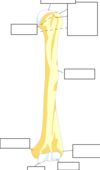

Label this diagram

Label this diagram of clavicle